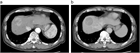

1. また、典型症例について画像を用いて解説した。詳細は本文を参照されたい。

1. ウイルス性肝硬変にて定期画像診断(サーベイランス)中に発見された肝細胞癌で、ガイドラインの治療アルゴリズムに沿って肝切除にて治療した症例である。